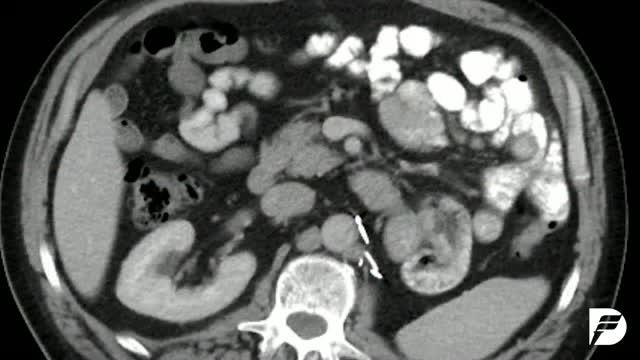

Image:

Dana-Farber Cancer Institute